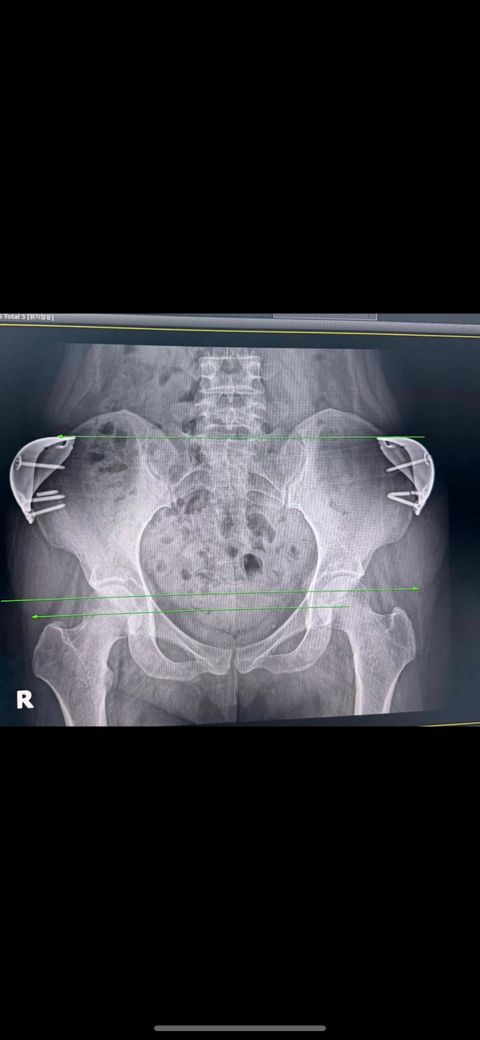

수술 부위에는 아직도 재수술 당시에 부러졌었던 금속 나사가 고정된 상태로 남아있고,

지금은 또 추가적으로 부러졌으며

다른 나사는 풀려서 빠지고 있는 모양도 엑스레이서 보입니다

박아둔 나사가 풀리고 부러져있고 새로 교체했던

실리콘마저 이동을 했거나 비대칭으로 삽입된걸

타병원 엑스레이

촬영을 통해 알게되었습니다

엑스레이 사진도 첨부 하겠습니다

사진은 개인 의료기록 일부이며 병원명을 특정하거나 명예를 훼손할 의도는 없습니다

단순히 제 상황을 설명하고자 올리는 것입니다